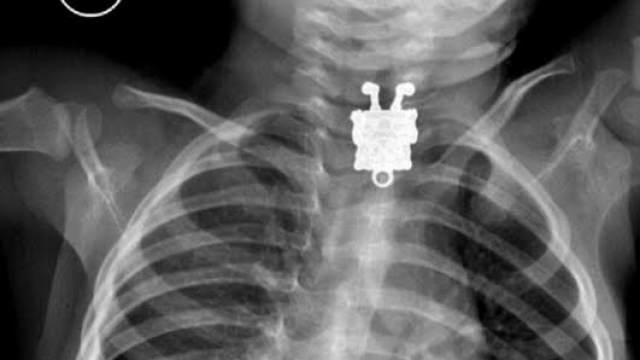

Fotografimi me rreze X ka zbuluar se në fytin e një bebeje gjendej një kapëse metali për qafore.

Fëmijes, i cili është vetëm 16 muajsh, i kishte ngecur figura e personazhit të filmave të animuar, SpongeBob. Ekipi i mjekëve të spitalit “Mbreti Abdylaziz” në Jeddah të Arabisë Saudite, e peruan menjëherë. Varësja e xjerr nga fyti i përkiste motrës së tij të madhe.

(er.cu/BalkanWeb)